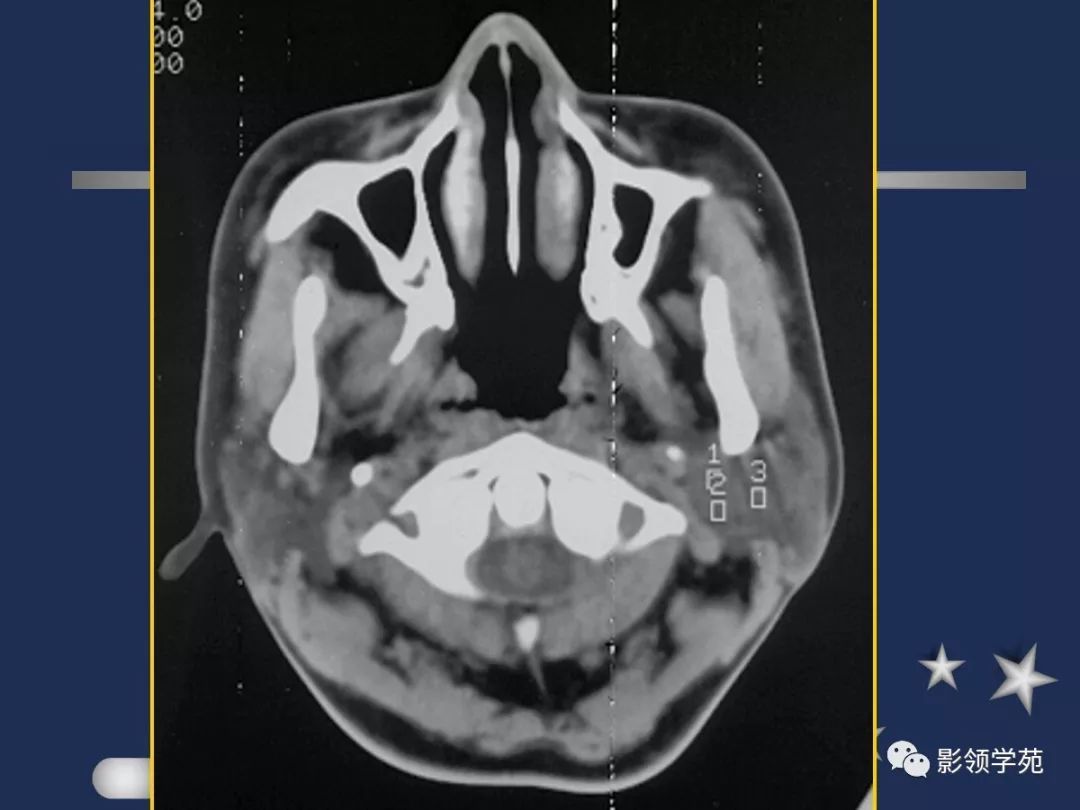

腮腺解剖

- 位于下颌骨后,胸锁乳突肌前,上致颅底,位于乳突尖和颞颌关节之间,下至下颌角,是茎突前咽旁间隙重要器官

- 腮腺是脂肪性腺体,CT呈低密度

- 腮腺内血管显示清楚